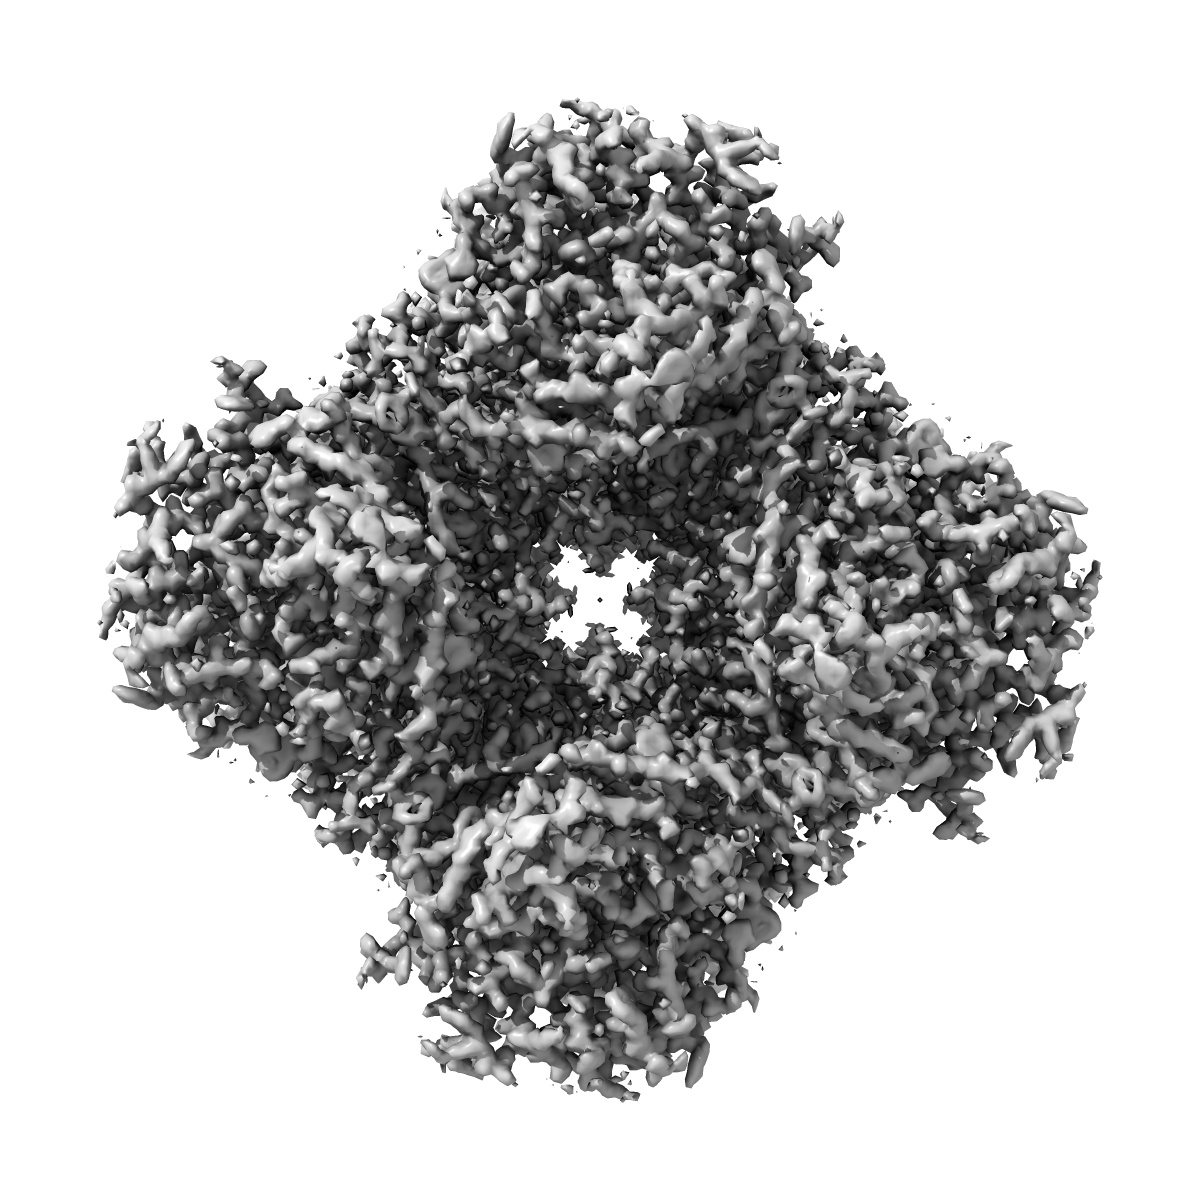

Cryo-EM structure of IMPDH2 bound to IMP and GAD

Single-particle1.82 Å

Sample: Ternary complex of IMPDH2 bound to IMP and GAD